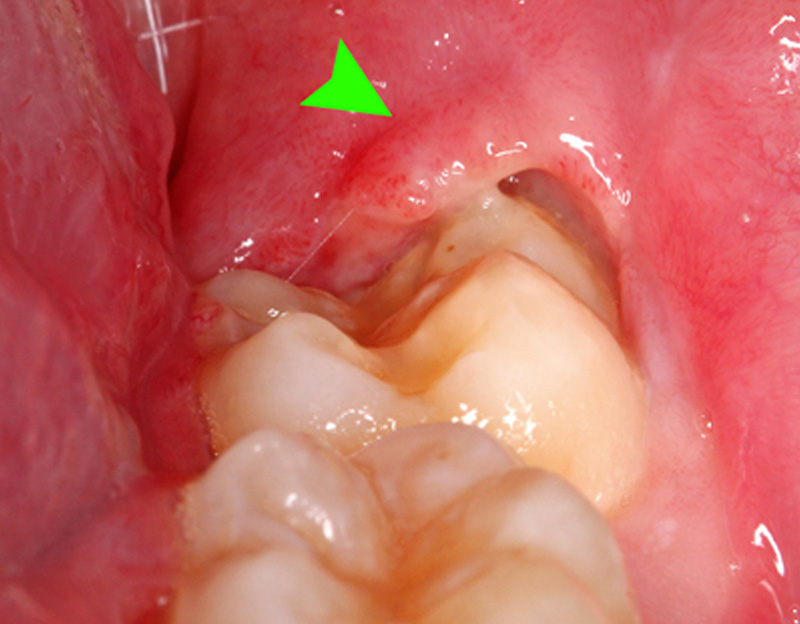

要拔智齿吗?如何预防智齿发炎?

西方社会曾有一波预防性拔智齿的趋势,跟曾经流行的阑尾切除类似,这是抱着智齿是退化器官的观念导致的错误医疗实践,可能多达数十亿颗牙齿的拔除是没有必要的。拔出智齿可能会导致术后疼痛,肿胀和颞下颌关节功能障碍。7 拔牙还可能损害牙龈并引起骨质流失,从而对第二颗磨牙产生不利影响。8

研究人员的结论是,大多数预防性拔除智齿是不必要的,正确的做法是对牙齿进行临床和X光片检查以判断是否有发生病理变化的可能,从而提示是否需要拔牙。在英国,通过使用严格的标准来确定是否有必要去除智齿,在中国,大部分牙科医生选择拔智齿,主要是因为智齿已经出现病变,或牙医根据经验预测智齿出现问题的概率从而给出适合的治疗方案。增加咀嚼锻炼、保持口腔清洁、保持充足睡眠、提高免疫力,都是预防智齿发炎的好方法。